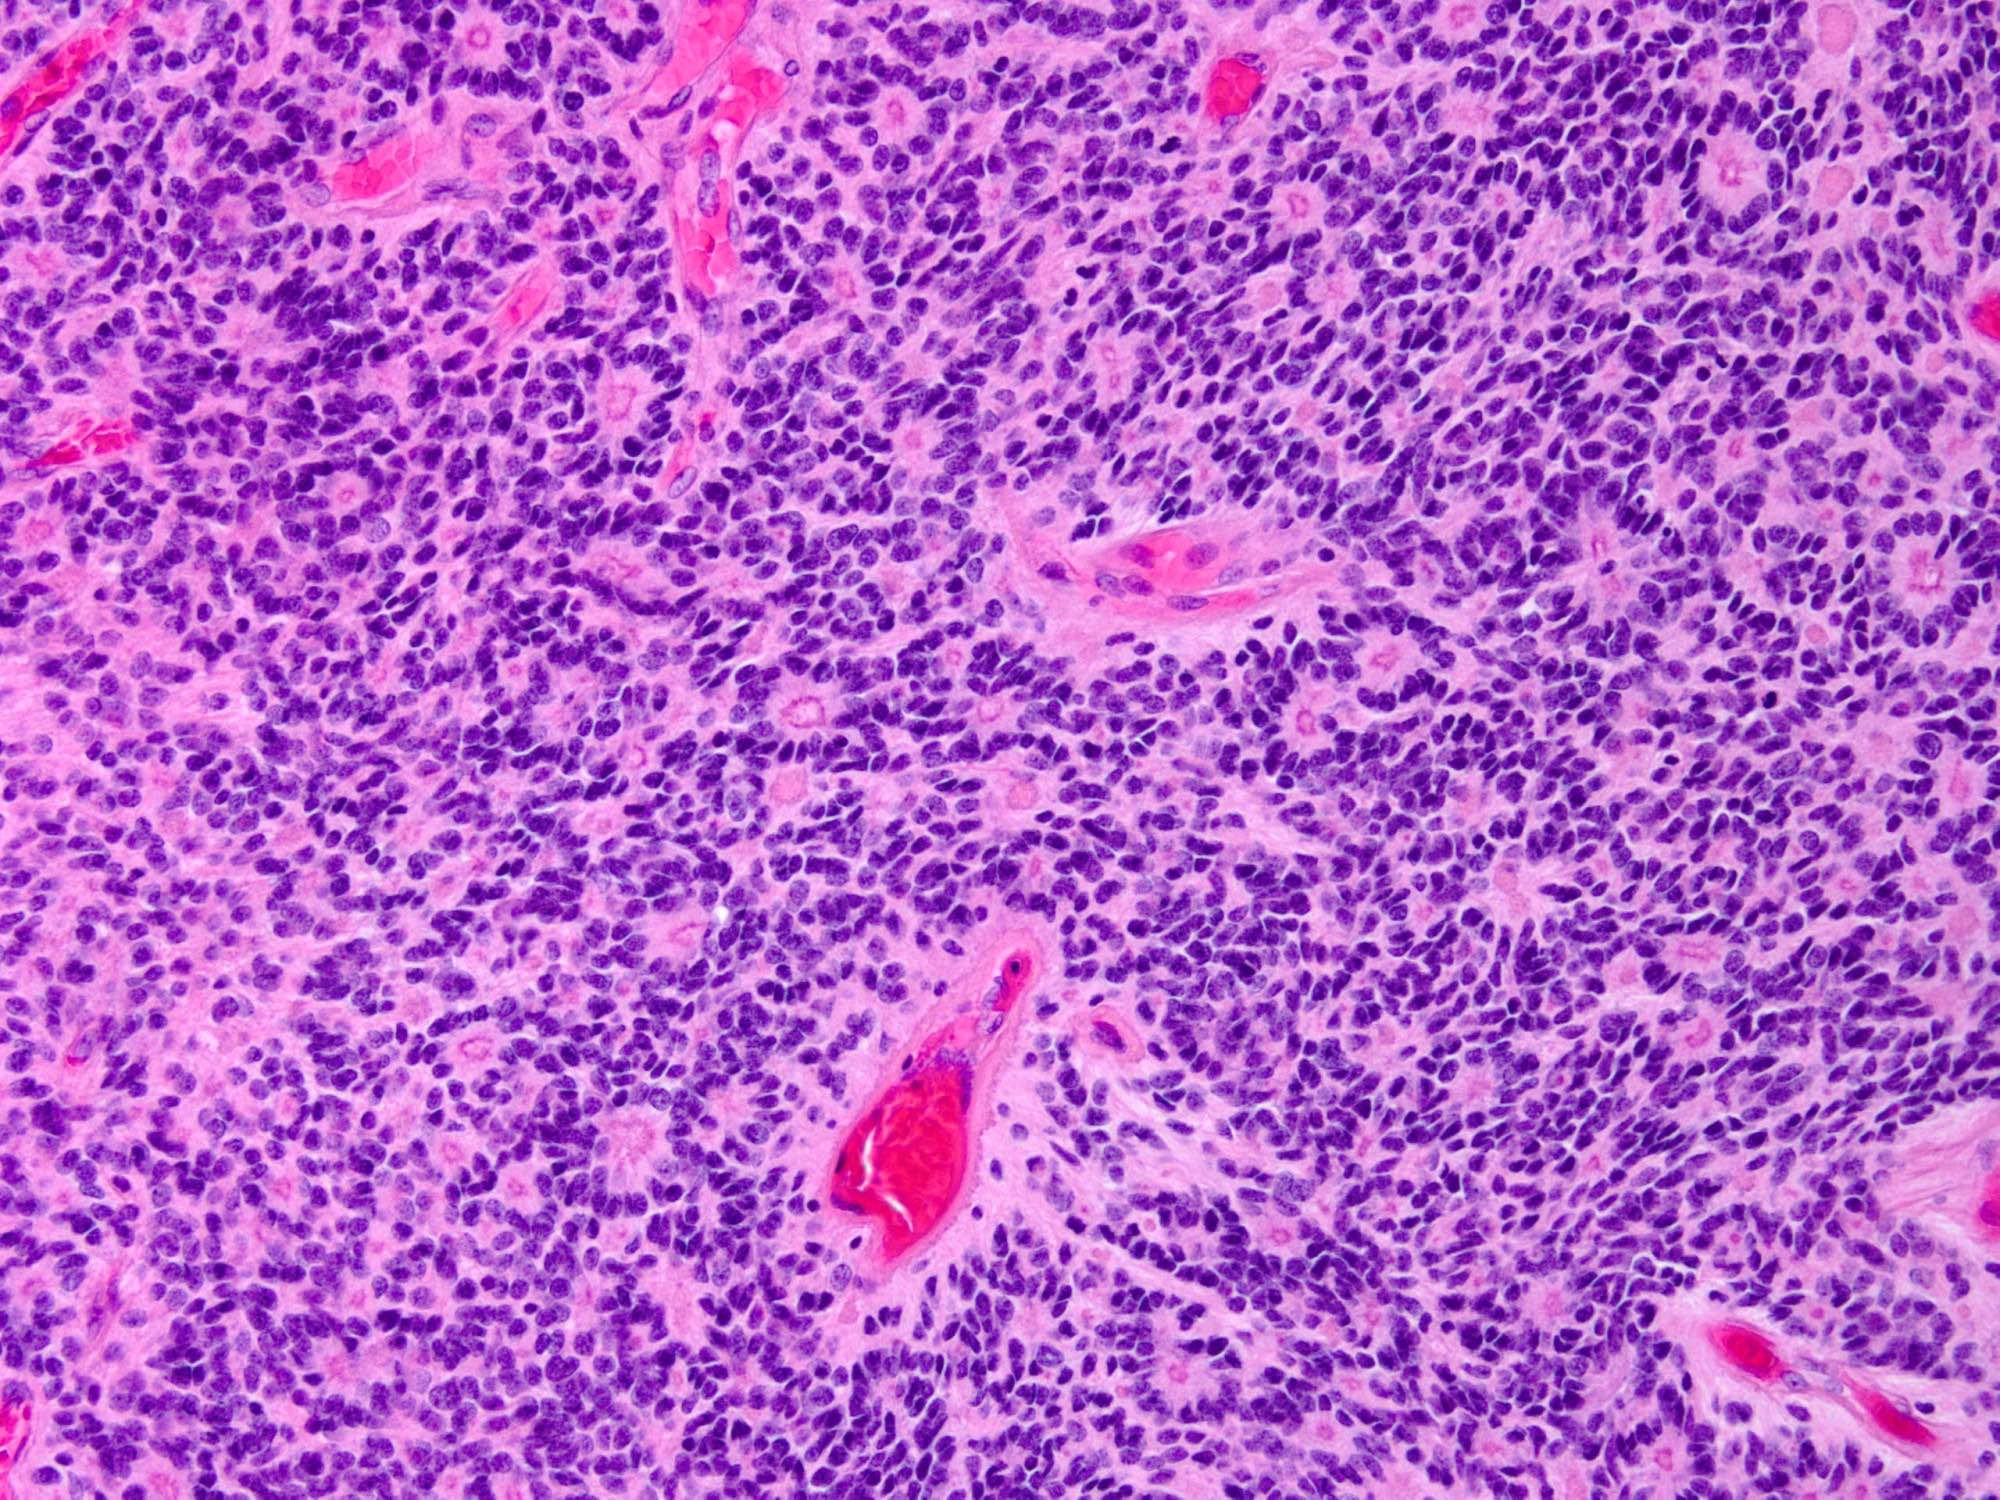

Microscopic (histologic) description

- Cellular tumor with typically sharply circumscribed borders; may be infiltrative

- Monomorphic round to oval cells with speckled chromatin

- Perivascular pseudorosettes, true ependymal rosettes, lumina and fibrillar areas

- May see gemistocyte-like cells and hypercellular nodules, particularly in posterior fossa tumors

- Can have nonpalisading necrosis, areas of cystic or myxoid degeneration, calcifications, degenerative atypia, neuronal differentiation and rarely metaplastic elements

- Morphologic subtypes have no clinicopathological significance and include papillary, clear cell and tanycytic

- Utility of histological grading is debated; the 2021 WHO still recommend assigning either WHO grade 2 or grade 3 to an ependymoma, according to its histopathological features as part of the integrated diagnosis

Microscopic (histologic) images